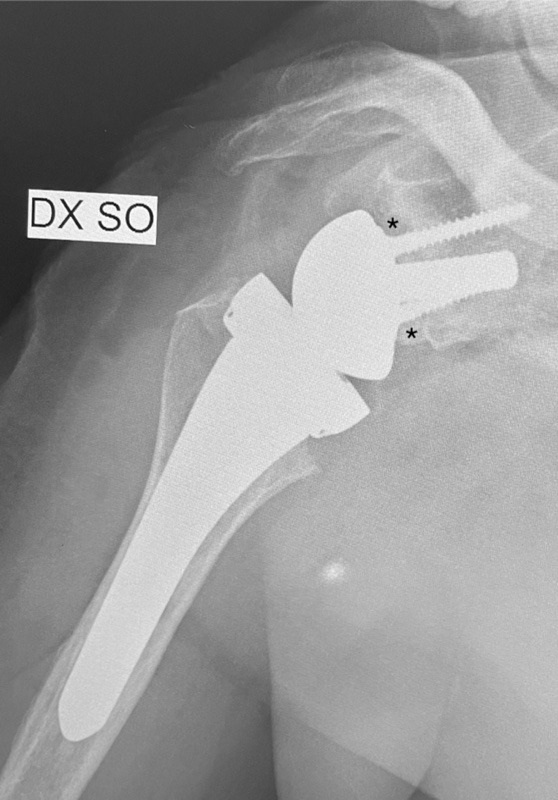

Dall’idea di Grammont (1985) la protesi inversa non ha subito grosse rivoluzioni per circa un ventennio. Una larga emisfera glenoidea e una componente omerale inclinata a 155° rispetto alla diafisi causano, rispettivamente, una medializzazione e un abbassamento del centro di rotazione. I principali problemi legati a questo impianto sono stati: lo scapular notching (contatto, e successiva usura ossea, tra il margine mediale della coppa omerale e collo scapolare) l’impingement, l’instabilità e l’usura del polietilene. La nuova generazione di protesi ha un angolo cervico diafisario di 135°-145° che ha ridotto la possibilità di impatto tra coppa omerale e collo scapolare8,9 (Fig. 2).

Lo stesso risultato può essere raggiungibile lateralizzando la glenosfera. Ciò può essere ottenuto o interponendo tra superficie articolare e metal back un tassello osseo prelevato o dalla testa omerale asportata o dalla cresta iliaca (BIO reverse)10 (Fig. 3), oppure creando un ulteriore spessore metallico.